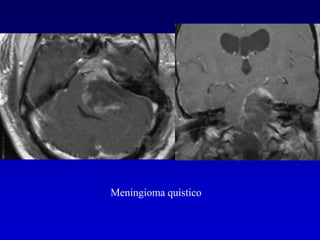

2 Meningiomas

Lesiones extraaxialesAumento de tamaño de la cisterna del APCTronco cerebral rotadoDeformación del 4 ventrículoZona de contacto de sustancia gris-blanca alrededor de la lesiónHendidura de LCR entre la masa y el parénquima

MeningiomaPuede invadir el CAI pero no es habitualmente su epicentroRealce dural

Meningioma quistico